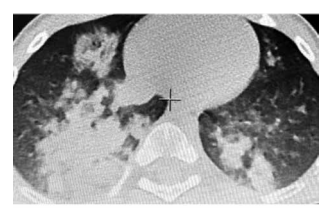

При коронавирусной инфекции SARS-CoV-2 стандартные технологии вентиляции не оправдали надежд и рекомендованы к применению только по жизненным показаниям. Альтернативой традиционной ИВЛ может стать интрапульмональная перкуссионная вентиляция легких.

В работе рассмотрены 3 клинических случая: пациенты, госпитализированные с COVID-пневмонией и тяжёлым острым респираторным синдромом, прошли курс процедур высокочастотной перкуссионной вентиляции (ВЧПВ). После ВЧПВ все пациенты демонстрировал...